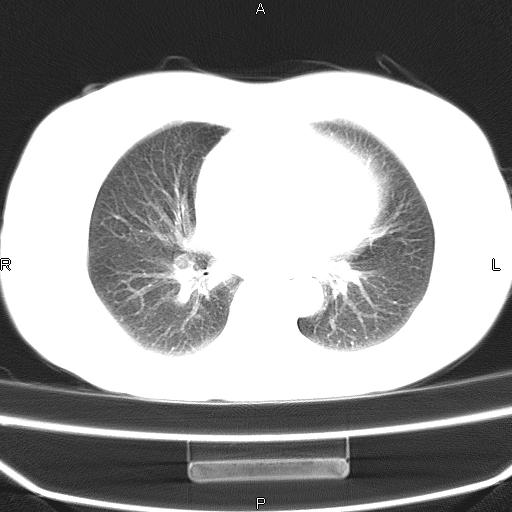

患者,女,66岁。健康体检胸部透视发现右上肺片状阴影。既往无不适,患者自诉三个月前曾有低热病史体温37.5左右一周。用药后缓解。至今无其它不适。请老师们指导指导。

考虑:右肺上叶周围型肺癌(分叶状肿块+砂粒状钙化+胸膜尾征)。

病灶见明显分叶、大小较大(大于3cm?),老年人,多考虑:肺癌,建议穿刺活检。

典型的中心型肺癌,尖段支气管阻塞。

以下是引用dyqct在2010-6-3 9:32:00的发言:[br]考虑:右肺上叶周围型肺癌(分叶状肿块+砂粒状钙化+胸膜尾征)。

不像中央型啊

周围性肺癌,

右肺上叶周围型肺癌可能性大。

考虑:右肺上叶周围型肺癌